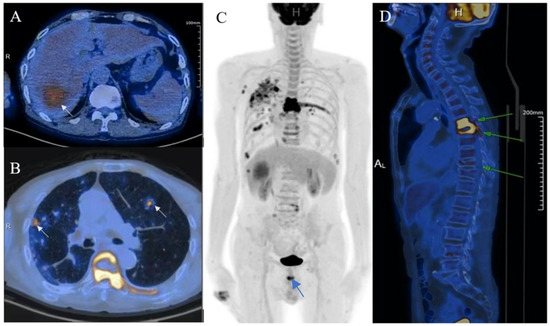

Ultrasound-Guided Coarse Needle Biopsy Diagnosed Isolated Hepatic Malignant Melanoma with Undetermined Origin in TB Patient: A Case Report

Chen, K.; Dong, Y.; Zhang, W.; Han, H.; Mao, F.; Zhang, H.; Wang, W. Ultrasound-Guided Coarse Needle Biopsy Diagnosed Isolated Hepatic Malignant Melanoma with Undetermined Origin in TB Patient: A Case Report. Diagnostics 2023, 13, 42. https://doi.org/10.3390/diagnostics13010042